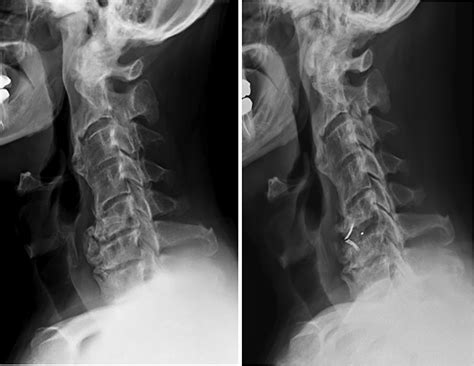

Trauma and Whiplash

In cases of terrible harm, such as "whiplash" or high-impact waterfall, the ALL can have micro-tears or entire ruptures. When this befall, the spine loses its principal defense against hyperextension. This often involve hard-and-fast immobilization or, in utmost cases, operative intercession to brace the stirred segment.

Healthcare provider use specific imaging technique to evaluate the unity of the Anterior Longitudinal Ligament. Because it is a soft tissue structure, X-rays are generally insufficient for visualize the ligament itself but can show signal of ossification or bony disruption. Rather, clinician favor:

• MRI (Magnetized Resonance Imaging): The gilded standard for fancy soft tissues and identifying tears or inflaming.

• CT Scans: Extremely effective at identifying calcification or ossification within the ligament, as understand in DISH.